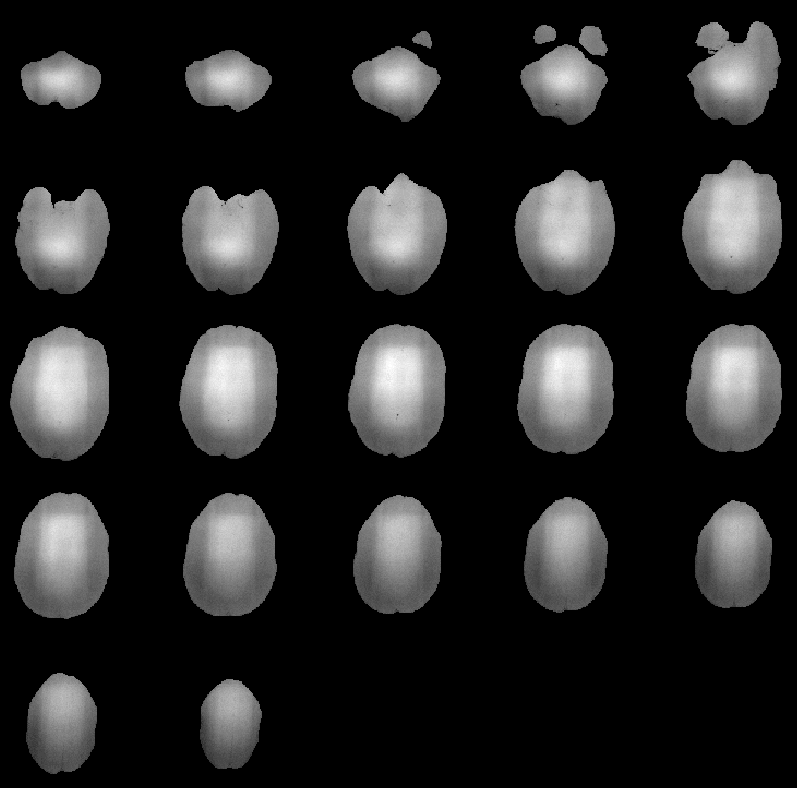

Figure 8.26 shows the RF inhomogeneity detected in Data Set 1 by the Correct Intensity process. Slice 16 of the PD-weighted volume, before and after intensity correction, is highlighted in Figure 8.27.

Figure 8.26: RF inhomogeneity detected in

MRI Data Set 1.